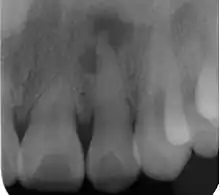

Radiograph (X-ray) showing microdontia. Note also periapical lesion on the maxillary left lateral incisor. | |

Microdontia is a condition in which one or more teeth appear smaller than normal. In the generalized form, all teeth are involved. In the localized form, only a few teeth are involved. The most common teeth affected are the upper lateral incisors and third molars.

Localized microdontia is also termed focal, or pseudo-microdontia. A single tooth is smaller than normal.[3] Localized microdontia is far more common than generalized microdontia,[2] and is often associated with hypodontia (reduced number of teeth).[1] The most commonly involved tooth in localized microdontia is the maxillary lateral incisor, which may also be shaped like an inverted cone (a "peg lateral").[3] Peg laterals typically occur on both sides,[2] and have short roots.[2] Inheritance may be involved,[2] and the frequency of microdontia in the upper laterals is just under 1%.[1] The second most commonly involved tooth is the maxillary third molars,[3] and after this supernumerary teeth.[3]